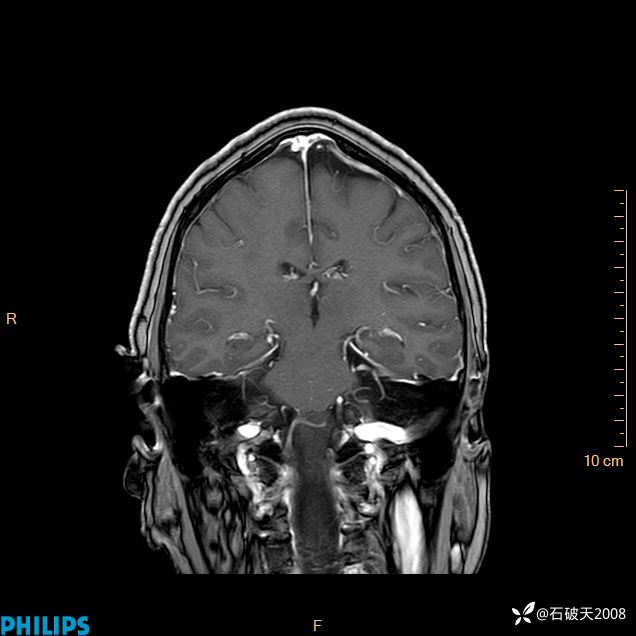

2020.11.14MR

增强冠状位